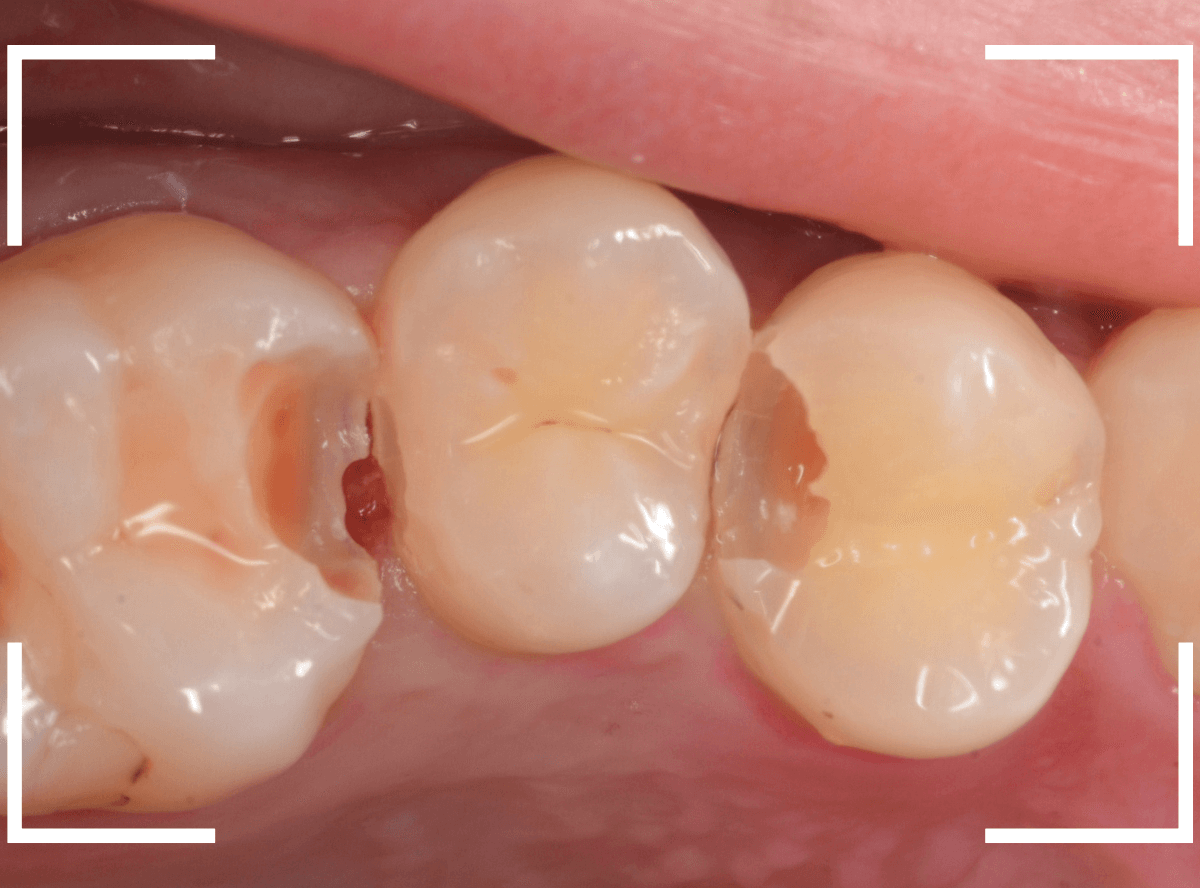

Case.22 痛みはないけど、歯のすきまから大きな虫歯

上の小臼歯の間が虫歯になっていた患者さんです。

症状はありませんし、見た目からも虫歯があるかはわかりませんでした。

レントゲン写真で確認します。

治療を開始します。

少し削ると、中からすぐに虫歯が出てきました。

ある程度、虫歯を除去したところで、う蝕検知液で確認します。

赤く染まっている部分が虫歯です。

まだまだ虫歯が中で残っている状況で、かなり深い虫歯なのが確認できます。

全ての虫歯を除去しました。

レントゲン写真からある程度確認出来ましたが、歯の神経スレスレまで虫歯が進行していました。

ここまで虫歯が進行していても、全く症状を感じない事も多いです。

そして、ある時急に痛みを感じるのです。

虫歯は急に進行しません。

治療後の定期検診で確実に食い止めましょう。